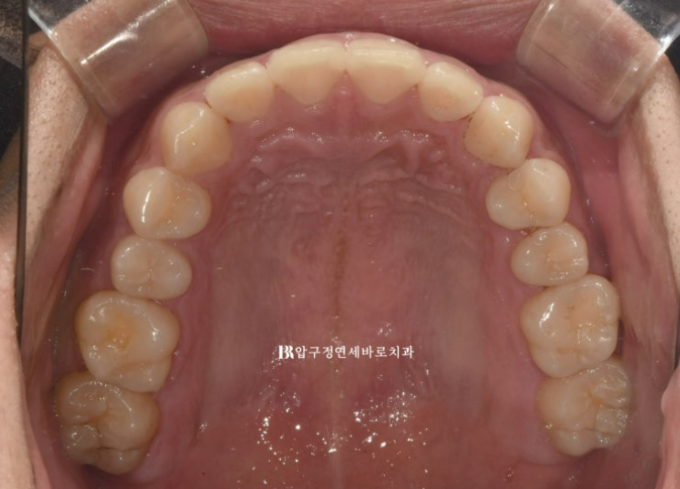

The upper teeth are aligned,

but one of the lower front teeth is crooked.

In particular, one of the lower front teeth shows an abnormal tooth shape.

The protruding part at the back is part of the tooth.

We decided to improve the tilted occlusal plane and deep bite with Invisalign Lite.

To resolve all of these issues within 14 aligners, it would be good to place one orthodontic mini-screw and use elastics as well.